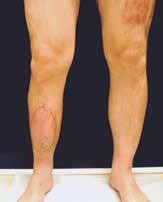

Sechs Monate später konnte bei solide eingeheiltem Knochenblock (Abb. 2f) eine teilgekoppelte Kniegelenkprothese implantiert werden, deren Bedeckung in der Folge durch die ausreichend dimensionierten Lappenplastiken unproblematisch war (Abb. 2g u. h). Der Patient erzielte nach Rehabilitationsmaßnahmen eine vollständige Belastungsfähigkeit bei freier Kniegelenkbeweglichkeit und solide verheiltem Integument (Abb. 2i u. j).